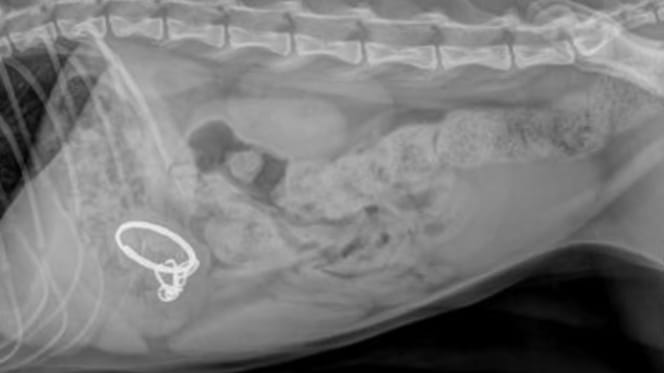

Röntgenbild von Kater Haru

Haru wird sofort in die Tierklinik gebracht. Als die Ärzte das Röntgenbild betrachten, weicht ihnen jede Farbe aus dem Gesicht. Im Magen des Katers befinden sich weitere, scharfkantige Teile des zerstörten Geräts. Ein Darmverschluss droht – und damit ein qualvoller Tod.